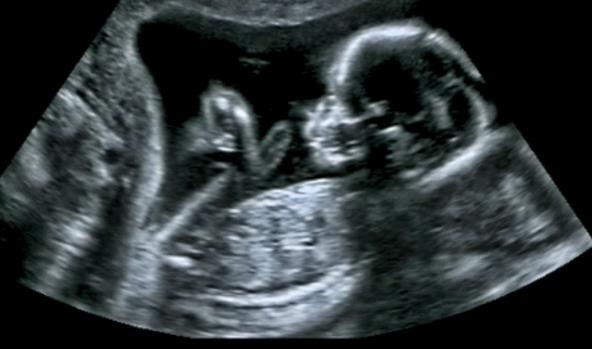

Uglavnom mislimo da su bebe u maminom stomaku pospane, mirne i tek ponekad vrlo aktivne kada šutiraju, okreću se ili štucaju. Ali zapravo, ovo su mali istraživači koje se na ovom najbezbednijem mestu na svetu zabavljaju, igraju dodirujući matericu, spuštaju se kao niz tobogan niz nju, piju amnionsku tečnost, nekada baš jako šutiraju kao da trče, a onda se kao i sve bebe, brzo umore, počnu da zevaju i na kraju polaku zaspu.

Otkrijte neverovatan svet mališana još u maminom stomaku u ovom preslatkom videu sa ulutrazvuka, koji će otopiti srca svih, a posebno roditelja koji očekuju bebu.